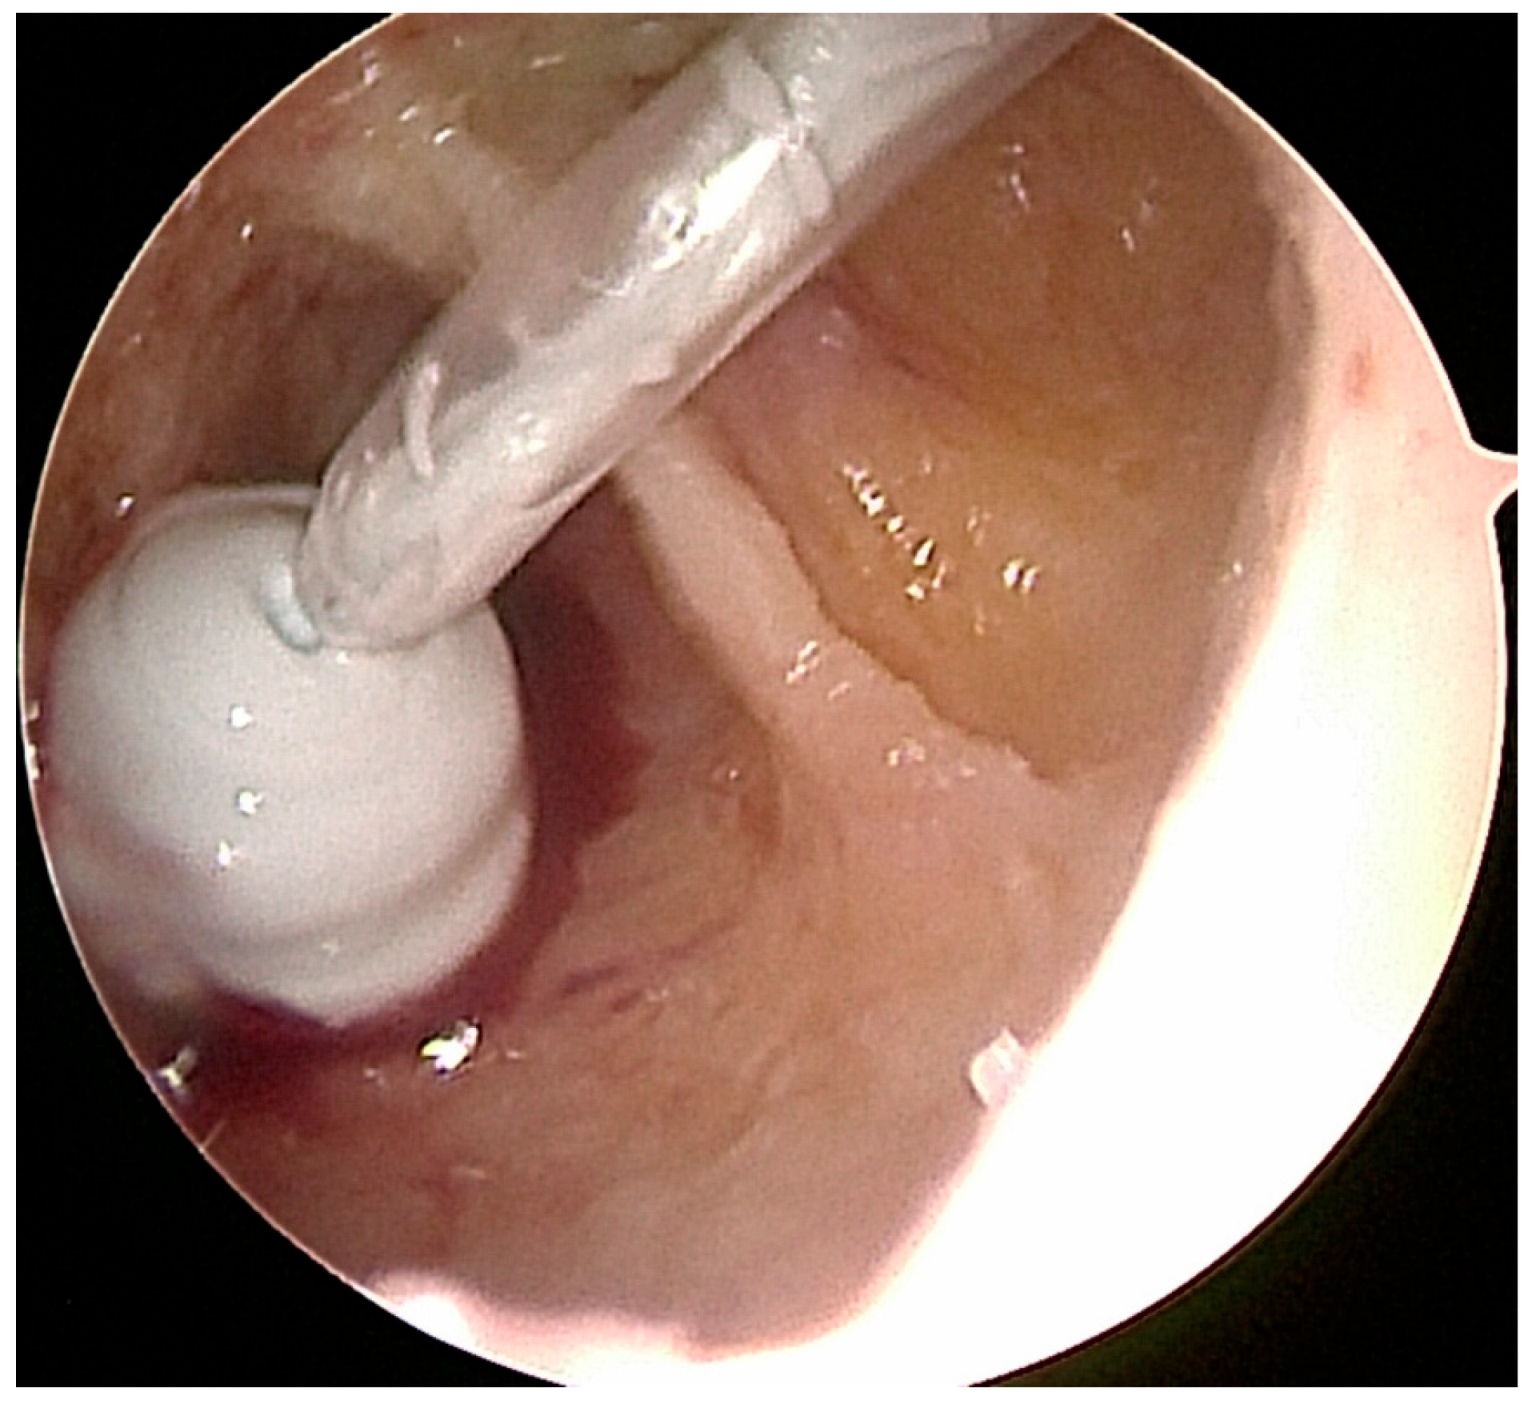

Figure 2.

After the introduction of the scope into the bone cavity, vision was often impaired by fat tissue in the case of IOL (a). After thorough irrigation and endoscopic removal of the fat tissue using an arthroscopic shaver, residual calcifications were removed using an arthroscopic grasper or shaver (b–d).